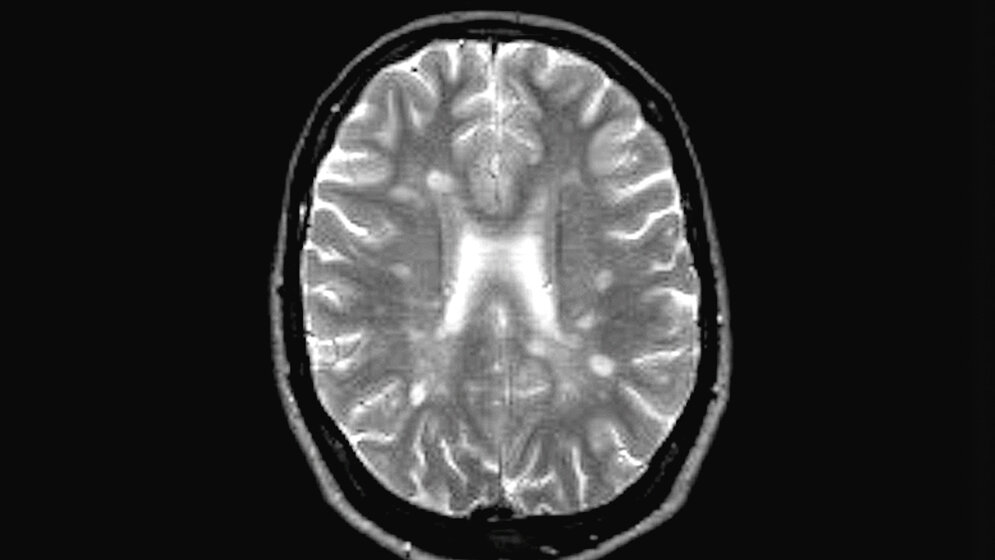

MRT zur Bildgebung

1981 wurde erstmalig durch den britischen Forscher Dr. Ian Young die Magnetresonanztomographie (MRT) zur Bildgebung bei einem MS-Patienten eingesetzt. Um die Empfindlichkeit der MRT-Aufnahmen zu erhöhen, wird „Gadolinium“ (Kontrastmittel) gespritzt. Dieses reichert sich in Entzündungsherden an, die erst kürzlich entstanden sind, wodurch sie besser zu erkennen sind, denn genau nach diesen Läsionen wird gesucht. Ein MRT kann die MS-Diagnose stützen und die Erkrankung auf ihrem Verlauf kontrollieren. Anzeichen für die Erkrankung konnten schon nach dem ersten Scan im MRT festgestellt werden. Auch wenn der Patient noch keine Symptome hat, kann die Erkrankung mit Hilfe des MRTs gesehen werden. Gerade in frühen Phasen der Erkrankung kann der Arzt anhand der Größe und der Zahl der Läsionen erkennen, ob mit einer Therapie begonnen werden sollte.